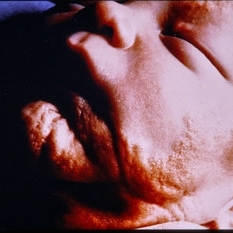

External Photo of Linear Sebaceous Nevus of Jadassohn

External Photo of Linear Sebaceous Nevus of Jadassohn

Feb 20 2015 by H. Michael Lambert, MD

External photo of linear sebaceous nevus of Jadassohn.

Condition/keywords: external, linear nevus sebaceous syndrome

External Photo of Linear Sebaceous Nevus Syndrome

External Photo of Linear Sebaceous Nevus Syndrome

Feb 20 2015 by H. Michael Lambert, MD

External photo of linear sebaceous nevus of Jadassohn.

Condition/keywords: linear nevus sebaceous syndrome, linear sebaceous nevus of Jadassohn